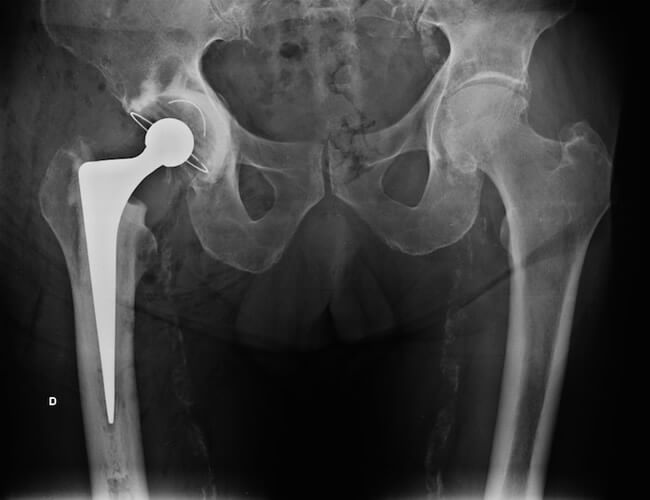

Fig. 7 - Exemplo de raio-x pós-operatório de prótese não cimentada

Obs.: Os exemplos de radiografias apresentados acima são de pacientes operados por mim e publicados com seu consentimento, preservando sua identidade.